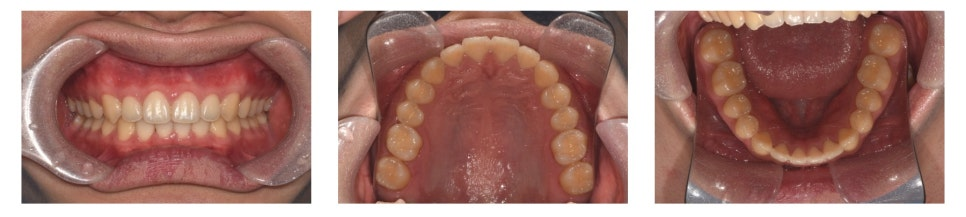

만 21세 남자 환자가 아래 앞니가 벌어졌다는 고민으로 찾아왔습니다.

초진 구내 사진을 보면,

▶ 아래 앞니 사이가 많이 벌어진 상태(spacing)

▶ 앞니가 깊게 물려 있는 상태(deep bite)

를 확인할 수 있었습니다.